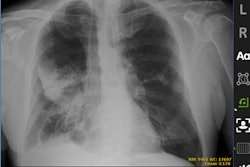

The team conducted a study that included 27,397 frontal chest x-rays consecutively obtained from August 2020 to April 2021 following deployment of the AI tool (Critical Care Suite, GE HealthCare) in the inpatient setting: 12,728 portable bedside chest x-rays were obtained using an AI-integrated scanner, which served as the AI group, and 14,669 chest x-rays were obtained using scanners without AI capability, which served as the control group.

According to the findings, the area under the ROC curve (AUC) for the AI tool was 78% with a sensitivity of 60% and specificity of 97%. When selecting for moderate to large pneumothorax, the AUC increased to 93%, and sensitivity and specificity increased to 89% and 96%.

In addition, the median reporting time in chest x-rays with radiologist-confirmed pneumothorax (PTx) was reduced by 46% in those with AI integration compared to those without AI integration (100 vs. 186 minutes, p < 0.001), the group found.